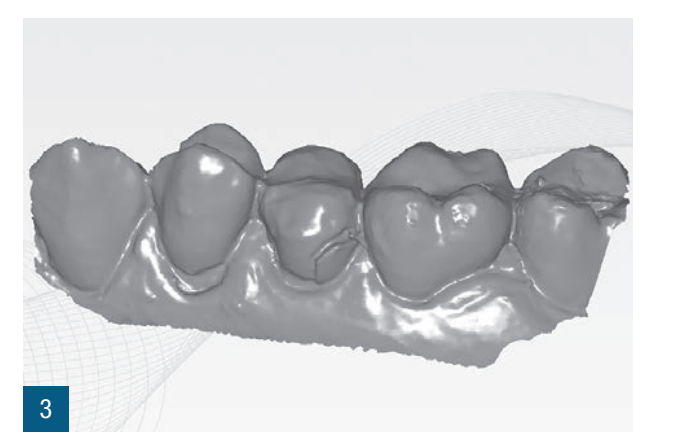

Пацієнтка 36 років звернулася до нас з частковим переломом коронки другого премоляра праворуч (1.5). Після перевірки неможливості консервативного відновлення було заплановано імплантно-протезне лікування з негайною екстракцією для заміни ураженого елемента (Рис. 1,2). Пацієнтка, не курець, була класифікована як ASA 1. Було виконано локалізовану CBCT в ураженій області для перевірки наявності та морфології вестибулярної кісткової стінки навколо елемента, що підлягає екстракції, в альвеолярному відростку. Перед екстракцією 1.5 була виконана цифрова внутрішньоротова відбитка (iTero Flex, Align Technology) зуба та прилеглих ділянок (Рис. 3). Після плескальної анестезії була виконана екстракція, обмежуючи травму пародонтальних тканин, розділяючи корені та використовуючи міні-важелі та синдесмотоми для збереження вестибулярної кісткової пластини. Оцінюючи цілісність альвеоли та сприятливі анатомічні умови, переходять до встановлення імплантату розмірів, що забезпечують адекватну первинну стабільність (4.1 x 11,5 TSVH ZimmerBiomet). Імплантат розміщується в близькій до піднебіння позиції відповідно до вказівок літератури (Рис. 6,7), заповнюючи проміжок між імплантатом та вестибулярною кістковою кортикою за допомогою гетерологічної кісткової пересадки (Copioss Zimmer-Biomet). Монтажний пристрій формують так, ніби це абатмент, і після його закручування на імплантаті проводять сканування. З цифрового внутрішньоротового сканування виконується CAD проектування гвинта загоєння (Рис. 4). У проекті буде використано як передекстраційне сканування, так і сканування з монтажним пристроєм, перетвореним в абатмент, щоб максимально точно відтворити гвинт загоєння. Морфологія гвинта загоєння відтворить існуючі тканинні умови на момент хірургії та дозволить уникнути естетичних дефектів у рожевій естетиці. Завершивши цифрове проектування, виконується 3D-друк з смоли (Lab2 Formlab) кастомізованого гвинта загоєння. Після завершення друку, отриманий гвинт загоєння з смоли Nextdent цементується з авто- та фото-твердим смолистим цементом (Relix Unicem, 3M) до абатмента, отриманого з монтажного пристрою, а потім закручується на імплантат (Рис. 5,6). Було проведено рентгенологічні контролі через три місяці та через рік (Рис. 7,8). Через 3 місяці була виготовлена остаточна коронка через цифровий потік з тим самим сканером та спеціальними сканбоді (Gentek, Zfx), які дозволяють ідентифікувати точне просторове положення імплантату. Через тиждень була передана остаточна монолітна коронка з фарбованої цирконії, закручена на ti-base (Рис. 9,10). Через рік було виконано ще одне сканування для оцінки з часом можливих об'ємних змін періімплантних тканин. Сканування, виконані на етапі передекстракції та через рік, були оброблені за допомогою спеціалізованого програмного забезпечення (meshlab) для оцінки розмірних змін (Рис.11-13).